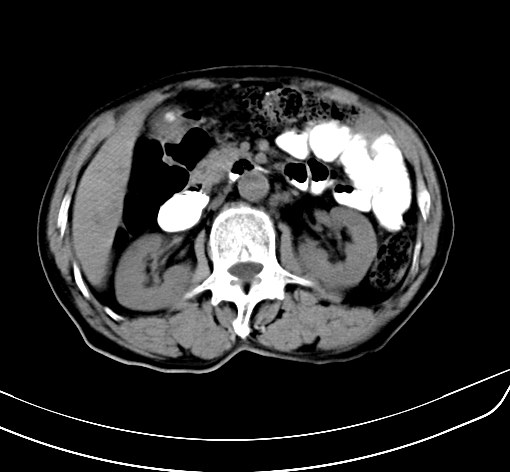

病人 男 70 咳嗽 胃部不适 2月余

胆囊壁增厚,与临近肝实质边界不清,临近肝实质内可见大片边界不清之低密度区,肝门区密度亦有减低,部分结构不清,尾叶前方可见块状影,肝右叶可见多枚边界不清之圆形低密度区,肝内胆管扩张征象,结合病史考虑1胆囊癌肝内转移,肝门区淋巴结转移,门脉癌栓待排2肝内胆管扩张3建议增强扫描

肝脏多发大小不等低密度灶,边界不清,肝门区结构不清,肝内胆管轻度扩张,胆囊密度不均匀,内见软组织样密度影,与相临肝脏边界不清.考虑:1、胆囊ca侵犯肝脏并肝内多发转移,肺上也有结节影,转移?建议强化扫描.2、胃充盈不好,如怀疑有病变最好建议做相关检查.

胆囊壁增厚,周围模糊不清,肝内多发低密度影,胃充盈欠佳,胃壁增厚,外形尚规整,考虑胆囊炎、胆囊癌肝内转移?建议胃肠道进一步检查或增强扫描。